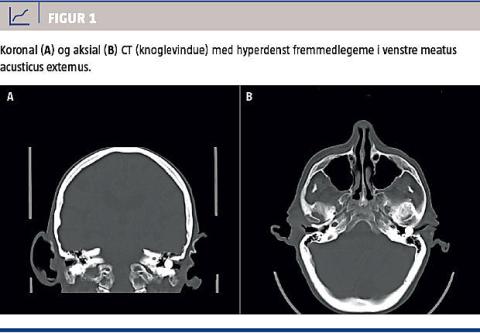

For at udelukke en cerebral årsag til patientens symptomer blev der udført CT af cerebrum, hvor man fandt alderssvarende forhold uden tegn til frisk infarkt, hæmoragi eller rumopfyldende processer. I venstre meatus acusticus externus sås et ca. 7 × 8 mm stort objekt med en CT-værdi på 3.000 HU, hvilket er foreneligt med metal (Figur 1).